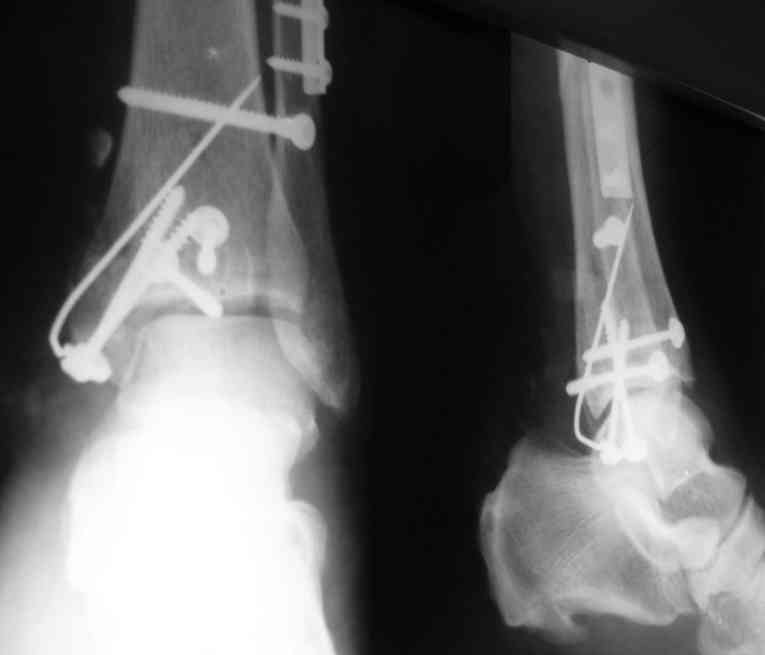

Уважаемые коллеги нужна помощь в определении тактики лечения: Больная Р.,1952 года рождения получила травму 18 августа 2007 года.

31 августа 2007 года была оперирована в другой области по поводу DS Закрытого двухлодыжечного перелома правой голени с подвывихом стопы кнаружи , кзади. Разрыв дистального межберцового синдесмоза. Перелом заднего края большеберцовой кости справа. Поступила в наше отделение со швами ,с некрозом медиальной поверхности правого голеностопного сустава. Проведено : снятие швов , антибиотики , некрэктомия с последующей кожной пластикой .Заживление 20 декабря 2007 года ,выписана из стационара . 3 марта 2008 года поступает с гиперемией , отек , флюктуацией. В настоящее время имеется рана по медиальной поверхности правой голени ,отеки и гиперемия сохраняется .Наша тактика:1) снятия воспалительного процесса, 2) удаление металлоконструкции, 3) выполнения артродеза правого голеностопного сустава.

Алексей20 15 Март 2008, 14:03

Не очень удачный вариант остеосинтеза: сохранен подвывих стопы, синдесмоз не достаточно репонирован. Думаю, в данном случае у пациента д-з: остеоартрит правого голеностопного сустава, послеоперационный остеомиелит правой голени. Предлагаю тактику: одномоментно выполнить удаление металлоконструкции, хирургическую обработку очага остеомиелита, резекцию голеностопного сустава, артродез аппаратом. Другие методы лечения не привидут к купированию гнойного процесса. Так как полость сустава в настоящее время имеет вид пиогенной капсулы, в которой будет поддерживаться гнойный процесс даже после заживления свища, с последующим его открытием и опорожнением гноя.